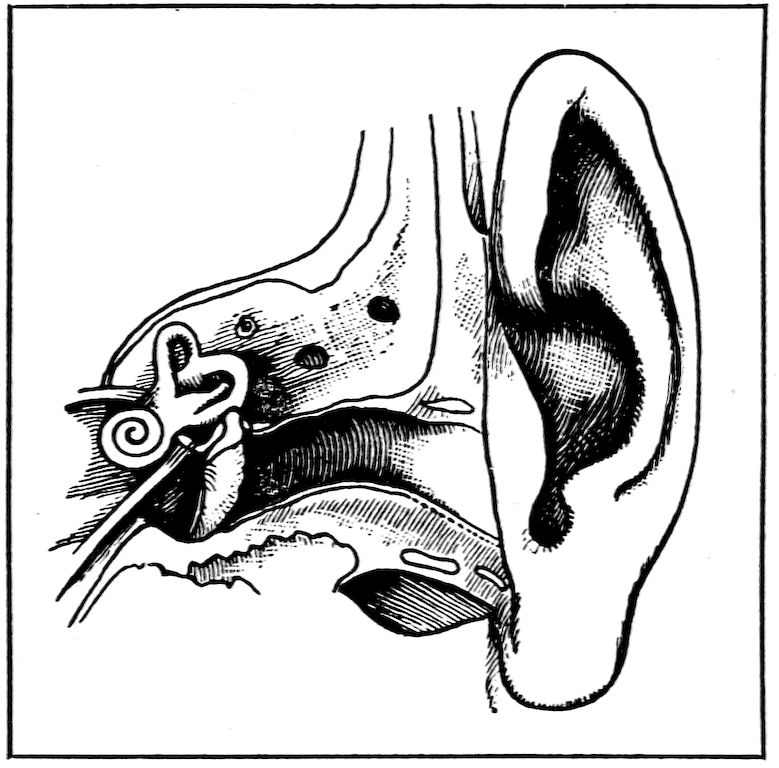

Strange as it may seem, the ears are even more delicate than the eyes, and more readily injured; and when hurt, there is less that science can do for them. The outer ear only catches sound and turns it inward. The parts of the ear that really hear are deep in 77the head, where they can be well protected. The little canal leading into the ear secretes wax, which hinders insects from crawling in. Sometimes they do get in, despite the wax. In some parts of this country, there are leeches that get into the ear. When they do this they cause great pain and often produce deafness. We should never try to pick or lift anything of this sort out of the ear. The best way, when anything alive gets into the ear, is to pour in a little quantity of oil. This nearly always causes the creature which has gotten in to back out, in order to escape the oil. If, instead of coming out, it is drowned, it must be removed by some skillful physician.

The Ear.

Showing the drum and bones.

Nothing should ever be inserted in the ear for the purpose of cleaning it except the little finger. The ear should be washed 78very carefully with soap and water and dried thoroughly. Sometimes, when swimming, people get water into their ears. They should shake it out at once, or the ears may ache. Sometimes water that gets in this way causes inflammation and cold, which hurt the sense of hearing. No one should ever strike another on the ear, even in play. It is likely to cause deafness. What is called the drum of the ear is a very delicate membrane which receives the sound. This is what really hears, and a blow on the side of the head may rupture this membrane and destroy the hearing.